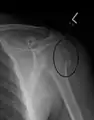

Fracture of the greater tuberosity of the humerus

Multi-fragmented, or comminuted fracture of the proximal humerus with involvement of the greater tuberosity